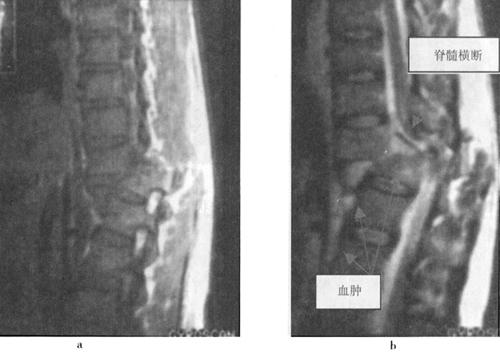

急性脊髓创伤常由于脊柱结构破坏(图7-12a和b),如撕裂伤、横断伤或严重挫伤,也可由内在的可逆性损伤如震荡或轻微挫伤引起,还可以由外来的可逆损伤如脊髓受压引起(图7-13)。按损伤程度分为脊髓震荡伤、脊髓挫伤、脊髓撕裂伤和横断伤。

图7-12a 颈段脊髓横断性损伤。颈椎正侧位片:C5以上前脱位,该水平段椎管狭窄,可推测脊髓受压迫

图7-12b MRI矢状面T1WI可见颈髓在C5水平明显受压,椎体前缘和椎管内可见中等偏高信号,局部颈髓可见斑点状高信号;12WI被压迫的脊髓亦见高信号出血灶,脊椎前方前纵韧带下血肿,呈高信号